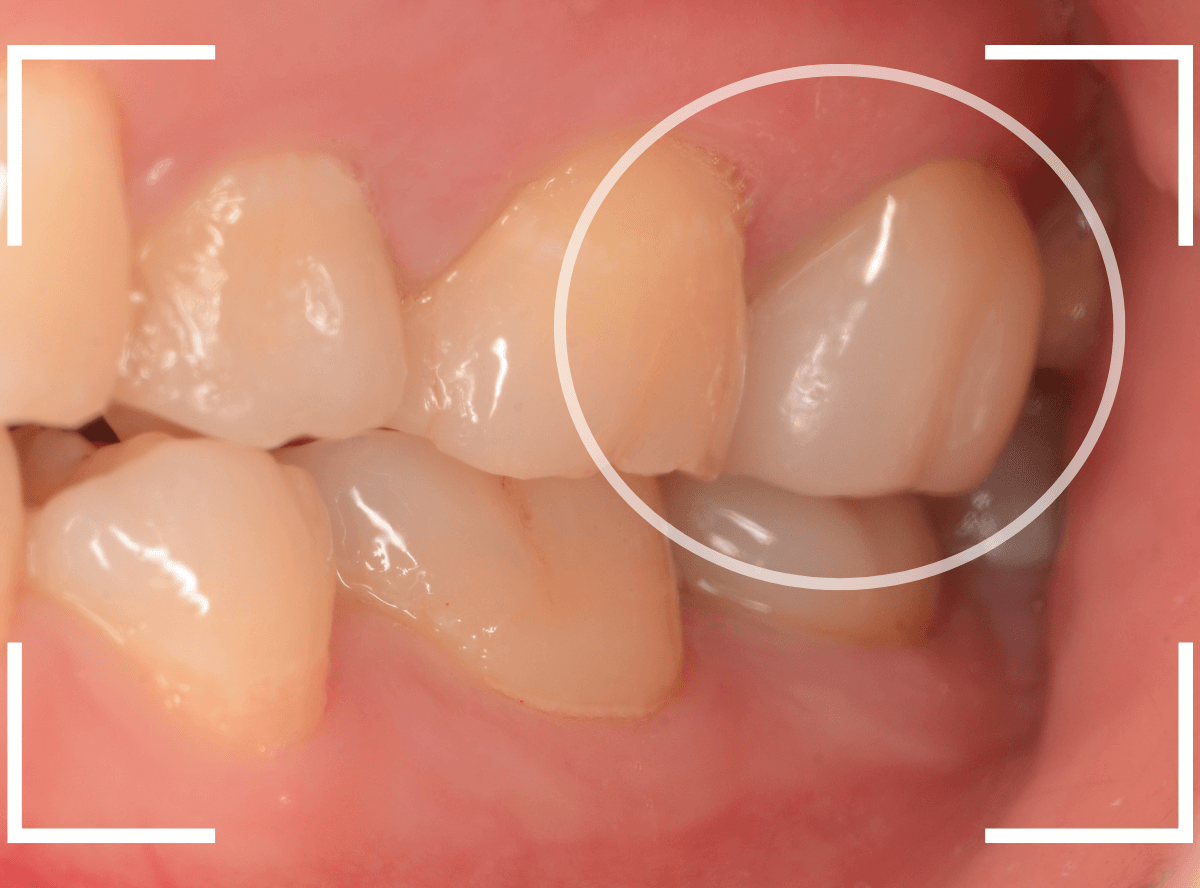

Case.19 メタル・クラウン、除去・再治療後、オール・ジルコニア・クラウンへ 4

今回は、上の奥歯の銀歯(メタル・クラウン)の中で虫歯になってしまった方です。

通常は、さし歯の中が虫歯になってしまうと、レントゲンにも写らず見つけづらいのですが・・・。

歯を裏側から見たところです。

幸い、見える部分に虫歯が

さし歯と歯肉の間に虫歯ができているのがわかります。

歯の奥まで虫歯が進んでいるのか、浅い虫歯ですんでいるのかは治療をしながら調べていく必要があります。